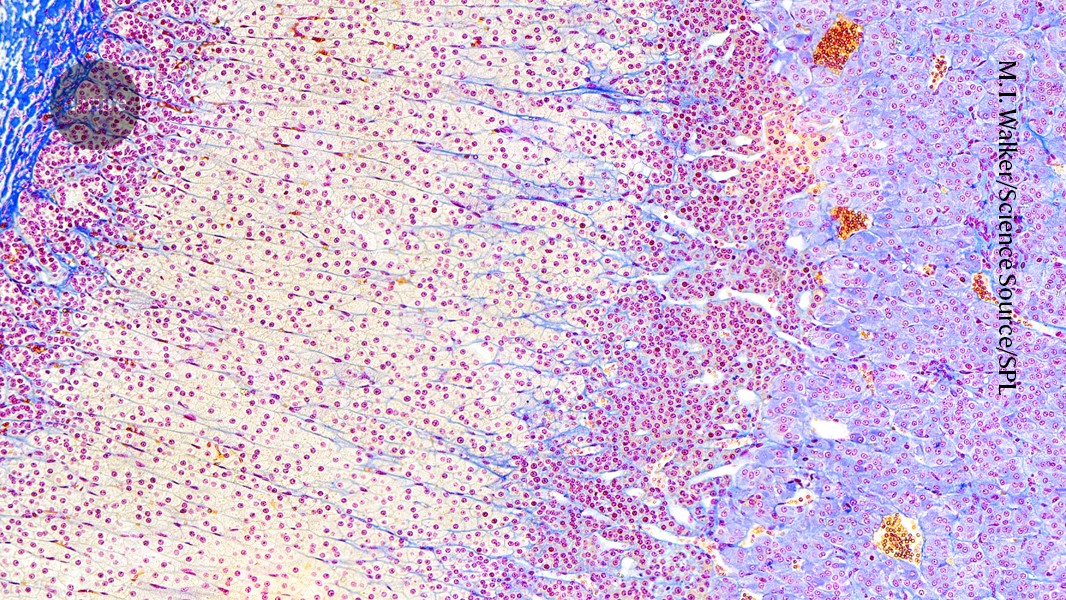

Scientists have successfully developed a laboratory-grown version of the adrenal cortex, an outer part of the adrenal gland that produces essential hormones for regulating metabolism, stress, and blood pressure. This "organoid," which mimics the function of secreting cortisol, a critical stress hormone, represents a first in medical research conducted as of October 21, 2025. The lab-grown structure could potentially be used to develop treatments for adrenal gland disorders. The development highlights advancements in biological techniques and offers new avenues for studying hormonal functions and diseases related to the adrenal cortex.